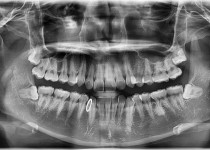

만 52세 전악 상악, 하악 전체 임플란트…

만 75세 상악 풀아치 증례

만 56세 상 하악 임플란트 증례

만 82세 하악 풀아치, 상악 임플란트(일…